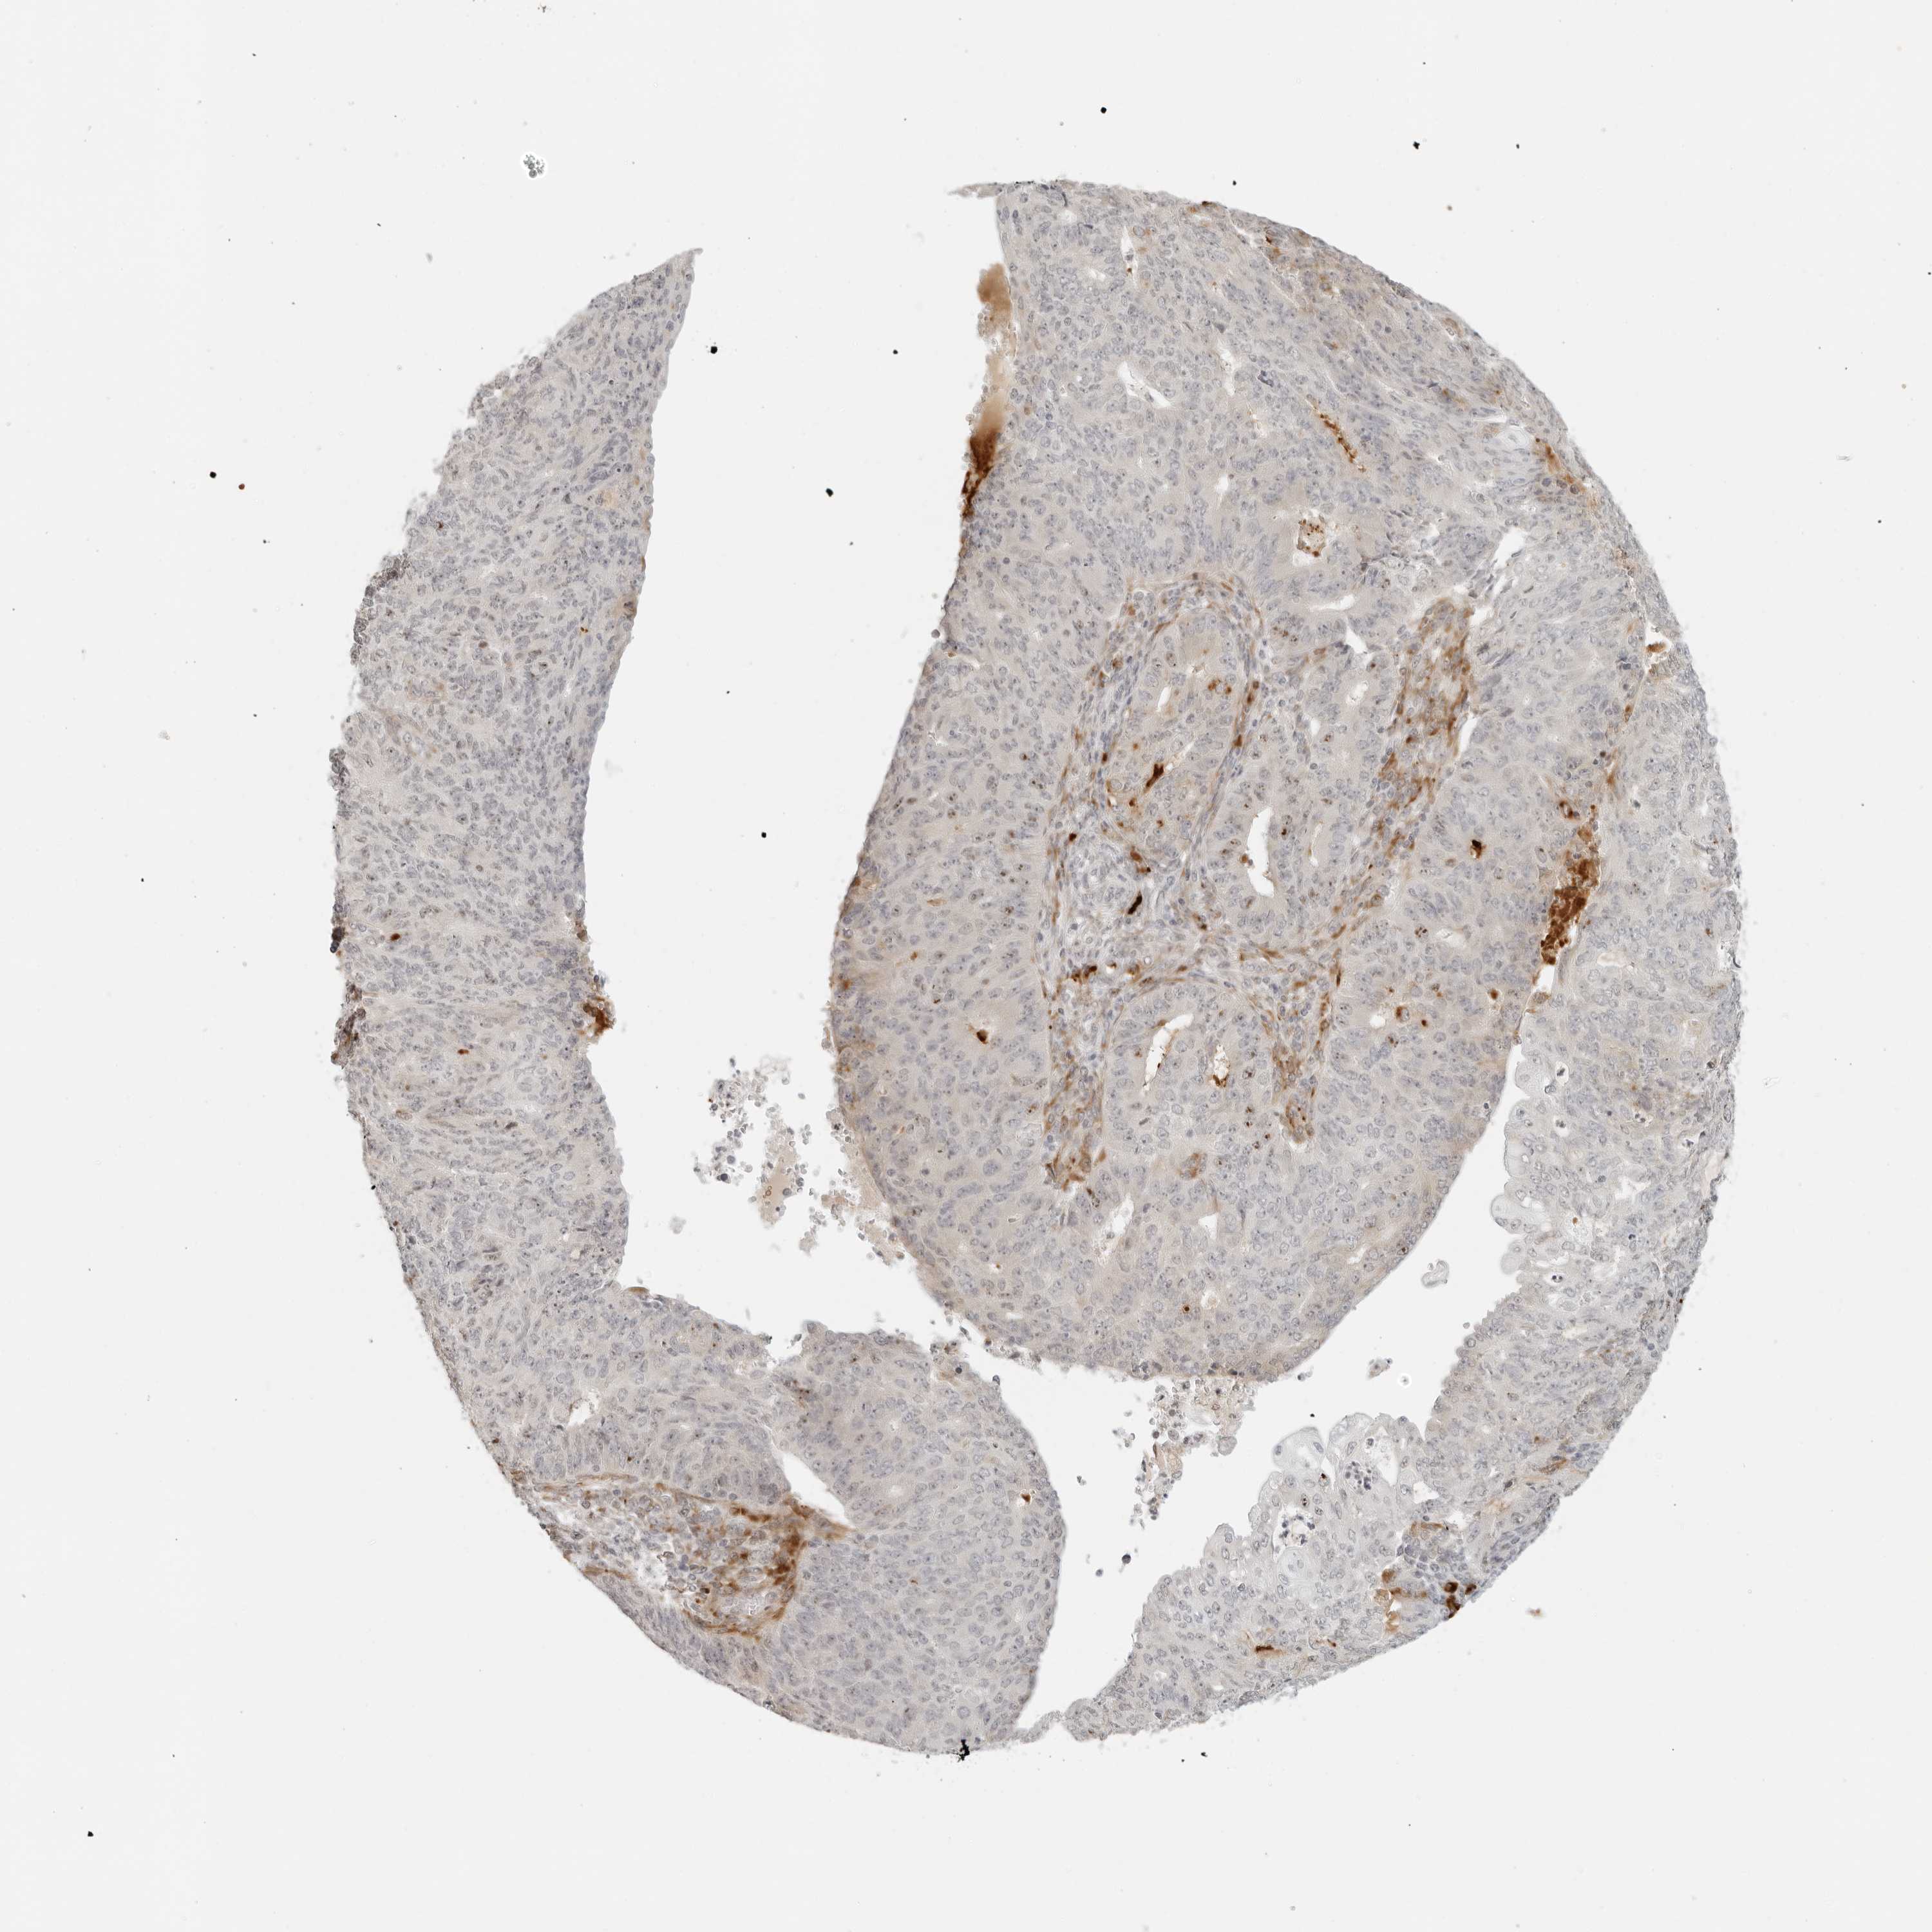

ENDOMETRIAL CANCER - Protein expressioni

A mouse-over function shows sample information and annotation data. Click on an image to view it in a full screen mode. Samples can be filtered based on level of antibody staining by selecting one or several of the following categories: high, medium, low and not detected. The assay and annotation is described here.

Note that samples used for immunohistochemistry by the Human Protein Atlas do not correspond to samples in the TCGA dataset.

Antibody stainingi

Antibody staining in the annotated cell types in the current human tissue is reported as not detected, low, medium, or high, based on conventional immunohistochemistry profiling in selected tissues. This score is based on the combination of the staining intensity and fraction of stained cells.

Each image is clickable and will lead to virtual microscopy that enables deeper exploration of all samples and also displays staining intensity scores, fraction scores and subcellular localization as well as patient and tissue information for each sample.

Antibody HPA028507

Staining

High

Medium

Low

Not detected

Intensity

Strong

Moderate

Weak

Negative

Quantity

>75%

75%-25%

<25%

None

Location

Nuclear

Cytoplasmic/membranous

Cytoplasmic/membranous,nuclear

Adenocarcinoma, NOS

Adenocarcinoma, metastatic, NOS